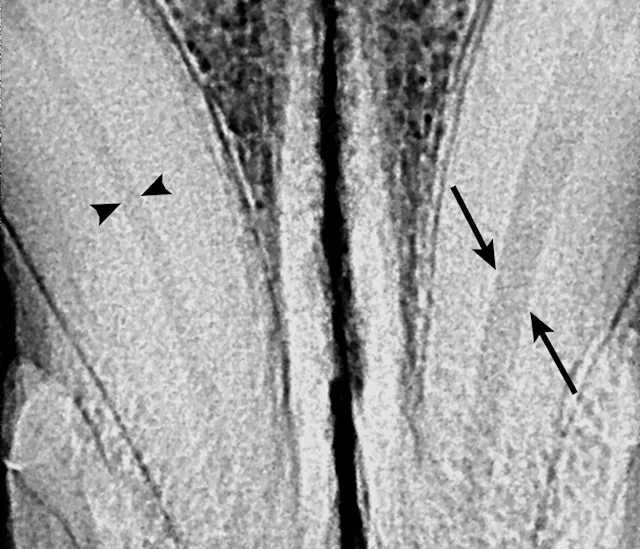

Enamel and/or dentin fractures can suggest that a tooth has been traumatized and may undergo irreversible pulpitis (Figure 1, above and Figure 2, below). Any tooth with a complicated crown fracture will become nonvital over time due to oral bacterial colonization of the pulp. Carious lesions can also irritate the pulp and cause pulpitis.

Dental radiography can be used to evaluate tooth structure anomalies and root pathology and to assess pulp canal size. Assessment of pulp canal size can be particularly useful for diagnosing nonvital teeth. A common misconception is that after a tooth dies, the canal becomes uniformly wider. In reality, the canal appears wider as compared with other canals because it stopped producing dentin at the time it became nonvital (Figure 7). Vital teeth with intact pulp have odontoblasts that will continue to produce secondary dentin, causing the pulp chamber to continue to narrow.4 Presence of periapical lucencies (Figure 8) and root resorption on dental radiographs are other indicators that a tooth is nonvital.

If the insult to the tooth happened recently, the pulp chamber size will be the same as the contralateral tooth. Repeat radiographs in 6 months may show that the pulp chambers of vital teeth will continue to narrow and the nonvital tooth pulp chamber will appear larger. Of note, it can be difficult to evaluate subtle changes in canal size in mature dogs with narrow canals.

The pulp chamber of the left mandibular canine (arrows) is significantly wider than the right (arrowheads), indicating that the pulp is no longer producing secondary dentin and is nonvital. Although this is a definitive sign of nonvitality, its absence does not confirm vitality.